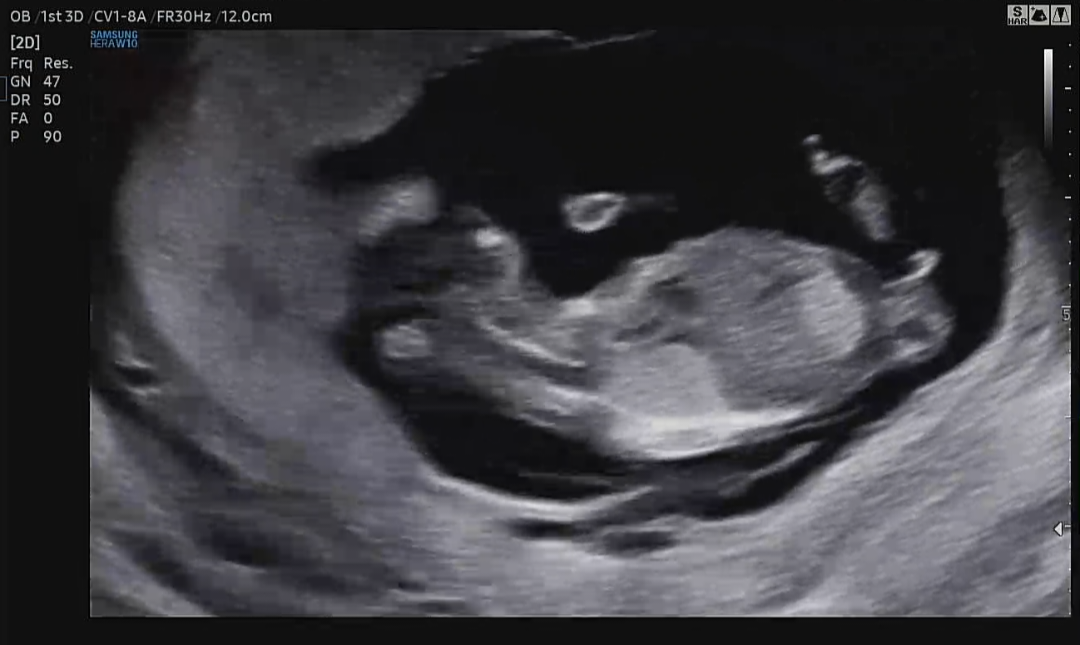

12주 1일차 초음파인데 입체초음파만 많이 보여주셔서 옆으로 누운 흑백 초음파가 많이 없어요 ㅠ ㅠ 이거로 혹시 성별 보이시나요?!

생식기 올라간걸로 보아 아들같아요